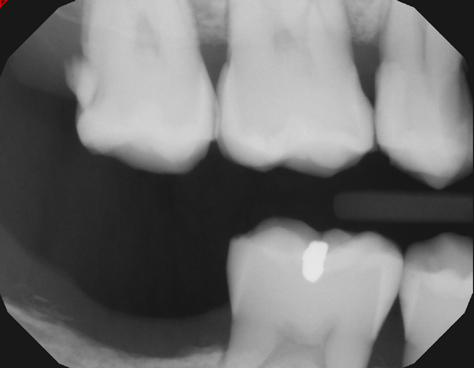

A 42-year-old male patient with a unremarkable health history presented in the AEGD Residency Program clinic with a chief complaint of pain in the mandibular right posterior area. Fig- ure 30 shows an unremarkable occlusal view of tooth No. 29; however, the radiograph showed deep distal caries near the root canal (Figure 31). Several treatment options were discussed with the patient, including extraction, root canal therapy, post and crown, and a distal occlusal composite that would later serve as a "margin elevation" material following endodontic therapy and preparation for a distal occlusal ceramic inlay or onlay. The patient chose the latter option.

Fig 31. Preoperative radiograph showing deep caries in canal. Restoration prior to endodontic therapy is required.

Figure 31